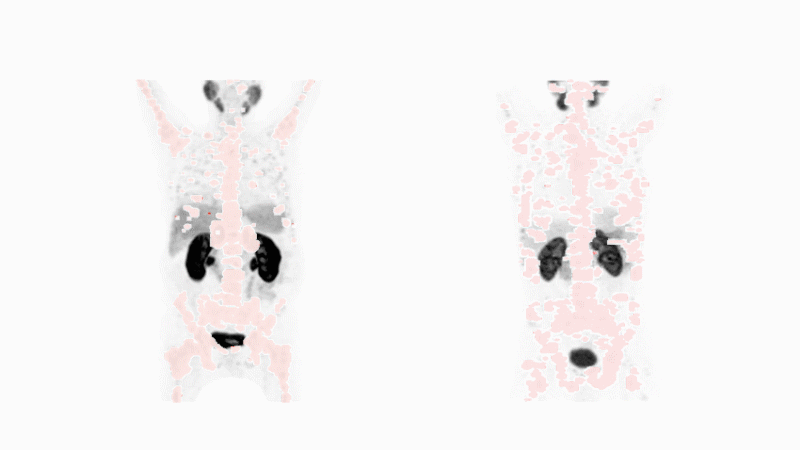

Die Nuklearmedizin wird auch in der Krebsdiagnostik verwendet: Die tumorspezifischen Moleküle docken an den Krebs an und geben über die radioaktive Komponente Gammastrahlen ab. Diese spezielle Strahlung kann von bildgebenden Geräten erkannt werden und zeigt an, wo im Körper sich Krebszellen befinden.

Snmmi animated image

Bild von Michael Hofman mit freundlicher Genehmigung von Journal of Nuclear Medicine. Animation von Fidelis Onwubueke

Konnte mittels dem tumorspezifischen Liganden Krebs in der Patientin oder im Patienten diagnostiziert werden, kann die gleiche tumorspezifische Komponente für die Radioliganden-Therapie verwendet werden.

Diese "see it, treat it"-Fähigkeit ermöglicht es den Ärzten, das richtige Medikament für die spezifische Krebsform der Patientin oder des Patienten zu wählen. Darüber hinaus können zukünftige Scans den Ärztinnen und Ärzten helfen festzustellen, ob das Medikament bei fortschreitender Behandlung wirkt.